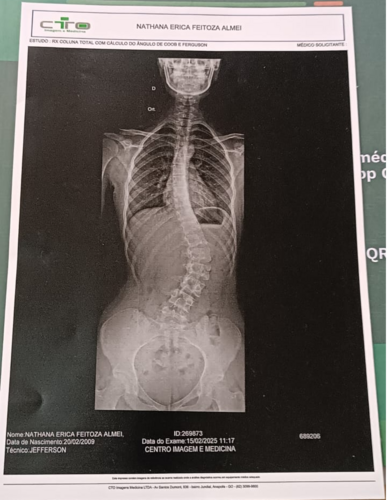

Nathana foi diagnosticada com escoliose grave, uma curvatura anormal na coluna vertebral. No caso dela, essa curvatura já atingiu 60 graus, o que está comprimindo seus pulmões e coração, provocando dores intensas, dificuldade para respirar e risco real de perder os movimentos das pernas ou de amputar partes delas.

⚠️ Se ela não operar, pode parar de andar.

Após inúmeras consultas, um neurocirurgião concluiu que o caso da Nathana não pode ser tratado com medicação nem com colete. A única saída é a cirurgia corretiva, com custo estimado em quase R$ 100 mil (veja abaixo o orçamento e os exames médicos que comprovam a necessidade urgente).

Segue as imagens da coluna e o orçamento da cirurgia.